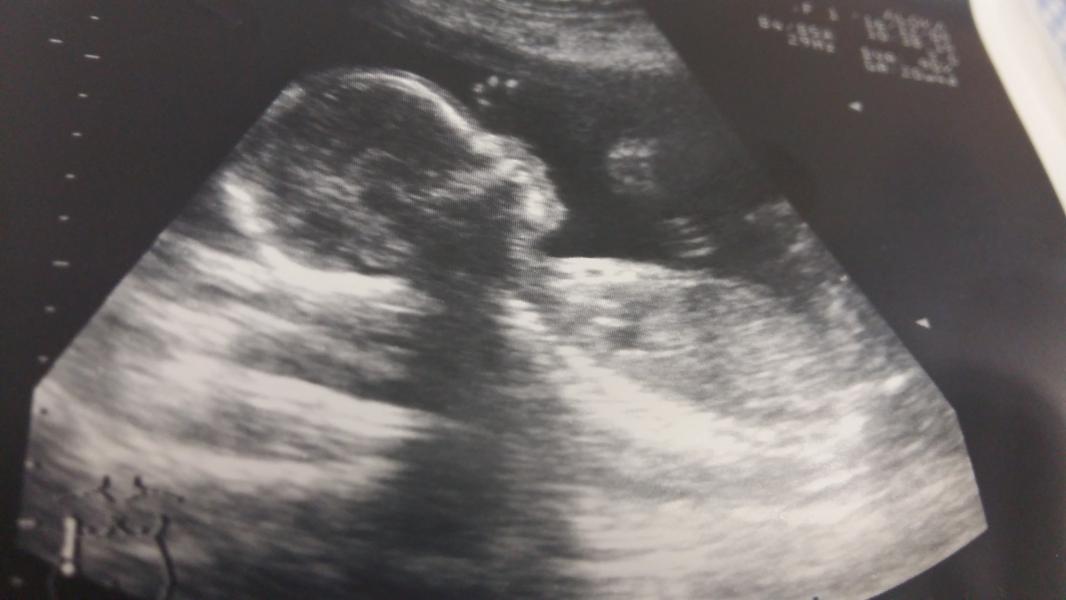

Сегодня прошла узи на Московской, врач с уверенностью подтвердил,что девочка,Виктория наша все время махала ручками😊 Конечно, он был немногословен,как и в прошлый раз, по заключению посмотрела вроде все хорошо, только в особенностях написано длина шейки матки 35 мм,внутренний зев закрыт. У меня срок 20.4 нед.

@iriska0807 спасибки😊 я с 10 ой попытки фотку выложила)я была у Пустового,второй раз к нему попадаю по бесплатному направлению от жк,а к гинекологу направление на консультацию дали в нииап к Крохмаль записалась